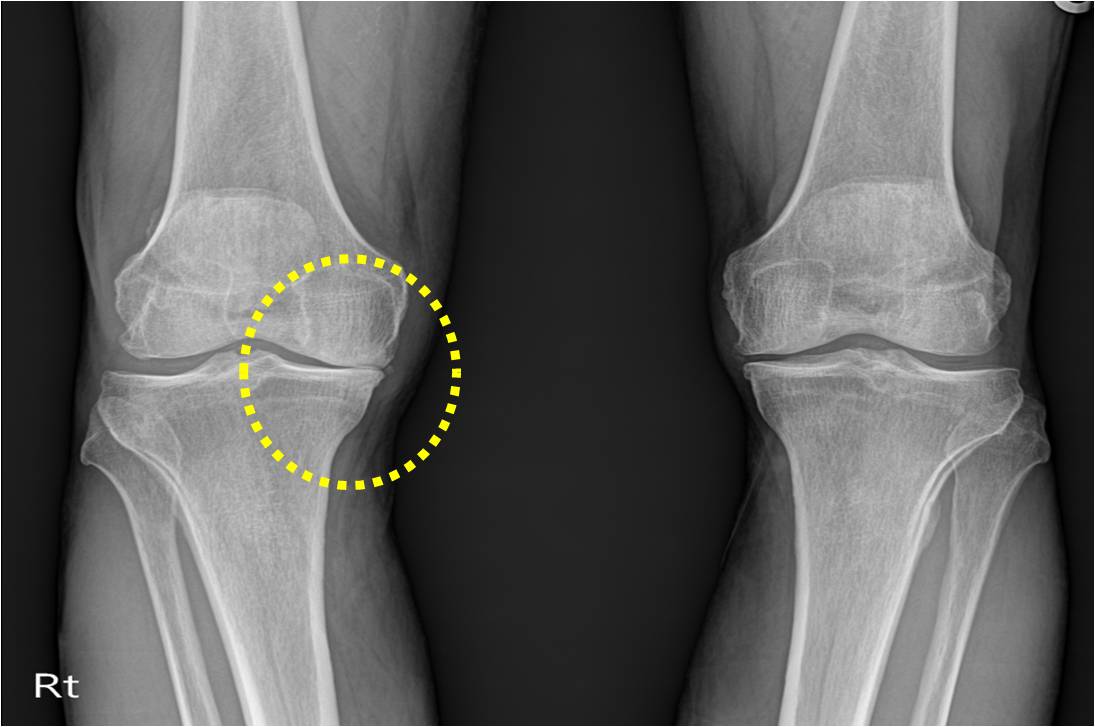

관절 건강에 도움이 되는 성분인 콘드로이친 입니다.나이가 들수록 뼈나 관절 등 신체기관들이 약해지는 건 어쩔 수 없죠. 특히나 무릎관절과 연관해서는 어르신분들이 많이 불편함을 호소하시는데요. 실제로 관절염 환자 중 60% 이상이 40~50대라고 해요. 그래서 최근엔 젊은 층에서도 관절건강에 대한 관심이 높아지고 있습니다. 이처럼 관절 통증 완화 및 연골 재생 효과가 있다고 알려진 콘드로이친 효능에 대해서도 알아보겠습니다.

콘드로이친 효능 1. 슬관절염 증상 완화

슬관절염은 슬관절의 연골 파괴와 염증으로 인해 발생하는 관절 질환으로, 통증, 염증, 강직성 등의 증상을 유발해요. 콘드로이친은 슬관절염 환자에서 통증 및 염증을 개선하는 데 도움이 돼요.

콘드로이친 효능은 연골 조직의 주요 구성 요소 중 한가지인 콘드로이틴 성분을 함유하고 있어요. 콘드로이친은 연골 조직의 재생과 보호에 기여하고, 슬관절의 염증을 줄이는 데도 효과가 있어요. 슬관절염 환자들이 콘드로이친을 복용하면, 연골 조직이 보호되어 연골 파괴가 줄어들고, 염증이 감소해서 슬관절 통증이 완화될 수 있어요.